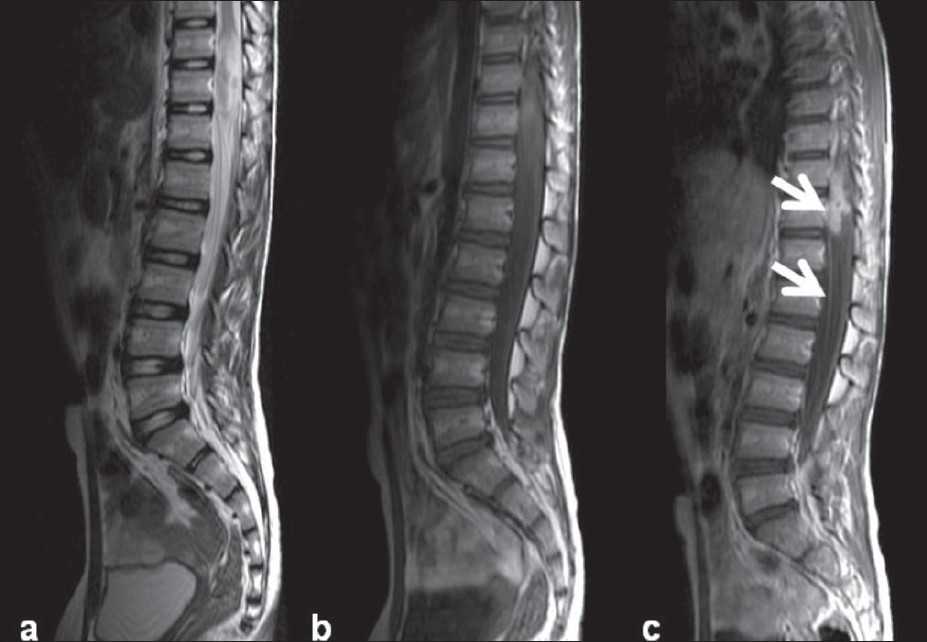

Туберкулез позвоночника (туберкулезный спондилит) – при отсутствии медицинской помощи этот недуг влечет за собой потерю трудоспособности пациента, паралич.

Начинается заболевание с поражения одного позвонка. В скором времени болезнь поражает близрасположенные костные отростки.

Происходит искривление позвоночного столба (сколиоз), вырастает горб (кифоз), это ведет к серьезным осложнениям.

В большинстве случаев диагностируют поражение грудного и поясничного отделов позвоночника.

- компьютерная томография — делается серия рентгеновских снимков под слегка разными углами, которые компьютер собирает в детальное изображение внутреннего строения вашего организма;

- магнитно-резонансная томография (МРТ) — с помощью сильных магнитных полей и радиоволн создается детальное изображение внутреннего строения вашего организма;